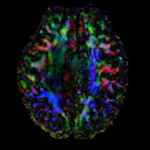

This is a classic case of a multi-sequence MRI exam we wish to spatially align to the anatomical reference scan (T1-SPGR). The scan of interest is the DTI image to be aligned for surgical planning/reference. The key points are: 1) the DWI sequence (EPI) contains distortions we seek to correct via non-rigid alignment; 2) the DTI baseline is similar in contrast to a T2, albeit at much lower resolution, but we do not have a T2 weighted anatomical scan, but instead a T1 and a FLAIR. So we use the FLAIR as the fixed image, because its contrast matches the DTI-baseline better than the T1, esp. in terms of tumor contrast.

MRI, brain, head, intra-subject, DTI, T1, T2, non-rigid, tumor, surgical planning

• Phase 3: resample DTI

1. Open the Resample DTI Volume module] (under All Modules menu; note this is distinct from the ResampleScalarVectorDWIVolume). We must use the ResampleDTI module to process tensor images to correctly resample the tensor data.

1. Input Volume: DTI

2. Output Volume: create new DTI Volume, rename to DTI_Xf2

3. Reference Volume: T2_Xf1

4. Transform Node: select "Xf2_DTI-T1" created above

5. check box: displacement

2. leave all other settings at defaults

3. Click Apply; runtime ~ 3 min.

4. set T1 or FLAIR as background and the new DTI_Xf2 volume as foreground

5. Move fade slider to see DTI overlay onto the structural image